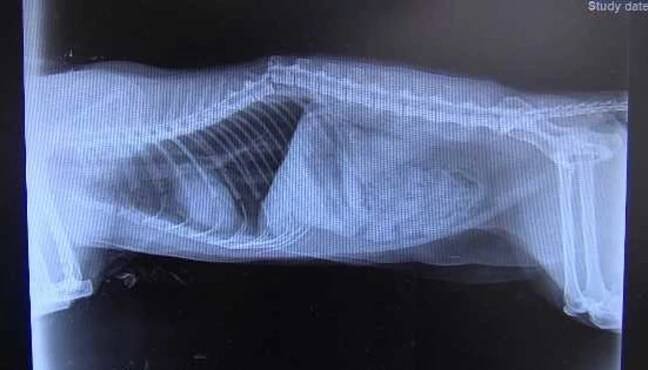

Bohužel velice smutní případ. Rentgen kočičky kterou majitele přinesli po napadení Rotweillerem který žil ve stejně domácnosti. Útok zlomil kočce celou páteř v polovině. Útok byl bohužel fatální.